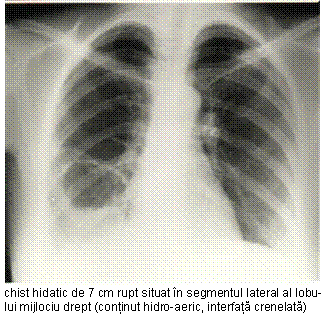

in stadiul de preruptura, fisurarea

bronsica este anun-tata de imaginea semilunara

clara situata la polul superior al opacitatii;

chistul deschis in arborele tra-heobronsic prezinta o cavitate bine conturata cu nivel lichi-dian si suprafata neregulata, ondulata, datorata membranei hidatice; cavitate balonizata dupa evacuarea completa a hidatidei printr-o fistula bron-sica cu rol de supapa unidirec-tionala;